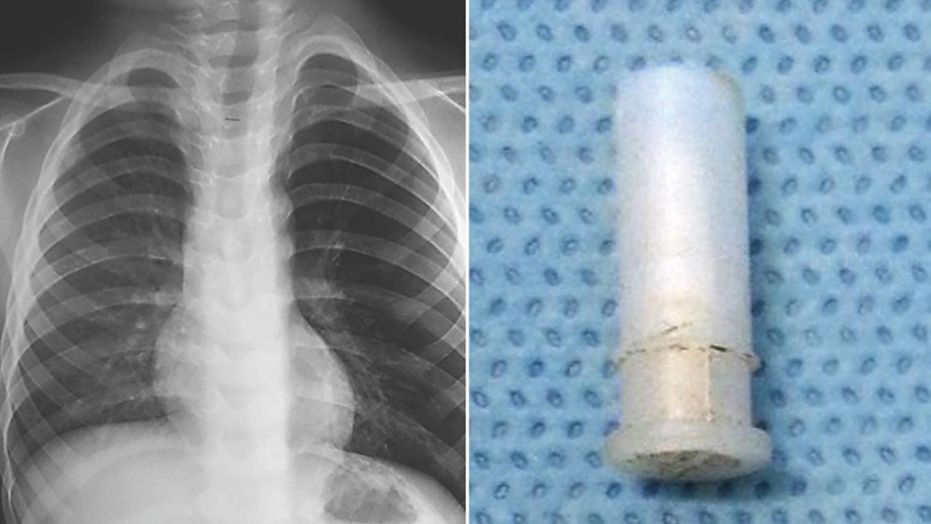

Al realizarle un examen de Rayos X, se dieron cuenta que el infante tenía un pulmón inflamado, debido a que “algo” bloqueaba el paso del aire, de acuerdo a un reporte de The New England Journal of Medicine en agosto 8.

El pequeño fue intervenido y se descubrió que había tragado un silbato que era el causante de su peculiar tono al toser. A sus 4 años, logró salir satisfactoriamente de la operación, pero antes su caso fue documentado en un vídeo que se viralizó por la web durante esta semana.